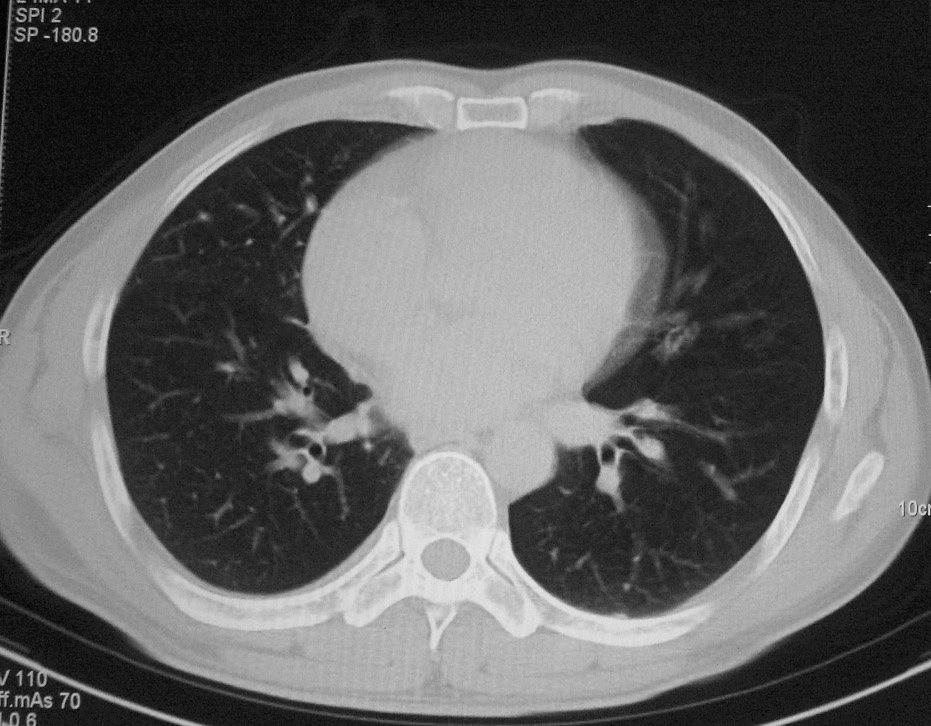

标题: CT5485:[原创]肺部占位请讨论

右肺上叶中央型肺癌并上叶肺不张、纵隔淋巴结肿大

右上叶支气管后壁明显增厚,支持右肺上叶中央型肺癌伴右上叶肺不张、纵隔淋巴结肿大。

右上叶支气管肺癌并右上叶阻塞性不张,右侧少量胸腔积液.

右上肺中央性肺癌伴右侧胸腔少量积液!右上肺胸膜下还有一小病灶,不完全排除结核,但个人支持恶性肿瘤!建议早穿刺活检。

右上叶支气管开口变窄,纵隔见肿大的淋巴结。支持右上叶中心型肺癌并右上叶不张纵隔淋巴结肿大。

右肺上叶中央型肺癌并上叶肺不张、纵隔淋巴结肿大.右侧少量胸腔积液。

右上肺中心型肺癌并肺不张,纵膈淋巴结肿大。右侧少量胸腔积液。